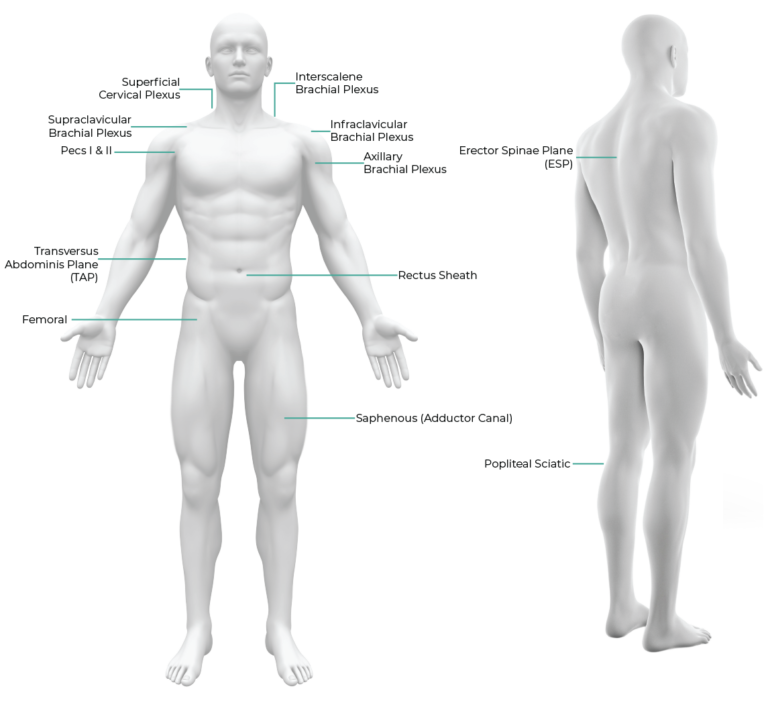

Nerveblox AI technology for ultrasound guidance is meticulously designed for anesthesiologists performing peripheral nerve block procedures and training. It is most valuable for applications requiring precision and those less frequent procedures that can be challenging due to their rarity – areas where AI capabilities outperform human attention. This versatility makes it an indispensable tool for highly skilled anesthesiologists who may require assistance with these uncommon procedures and peace of mind for image interpretation, especially regarding sonoanatomy.

Furthermore, our technology extends beyond anesthesiologists who are experts in ultrasound imaging. Anesthesiologists, including general practitioners, emergency medicine doctors, who may not possess specialized ultrasound training, can harness the power of our AI technology. Nerveblox provides standard, more accurate, and reliable peripheral nerve block guidance for them. This inclusivity ensures that anesthesiologists across all expertise levels can provide enhanced patient care through the utilization of advanced ultrasound technology tailored to peripheral nerve block procedures and training.